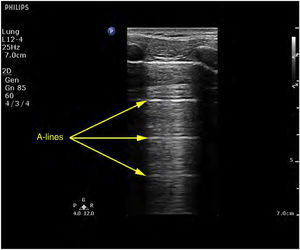

Ultrasound patternsPattern A: characterized by the presence of “sliding” (Video 1), and the artifacts defining it are the A-lines (Fig. 4).5,7 On exploring in M mode, we observe the “seashore sign” (Suppl. Fig. 2).5

A lines (Fig. 4): These indicate the presence of air in the chest. This finding is always present in the diagnosis of pneumothorax.